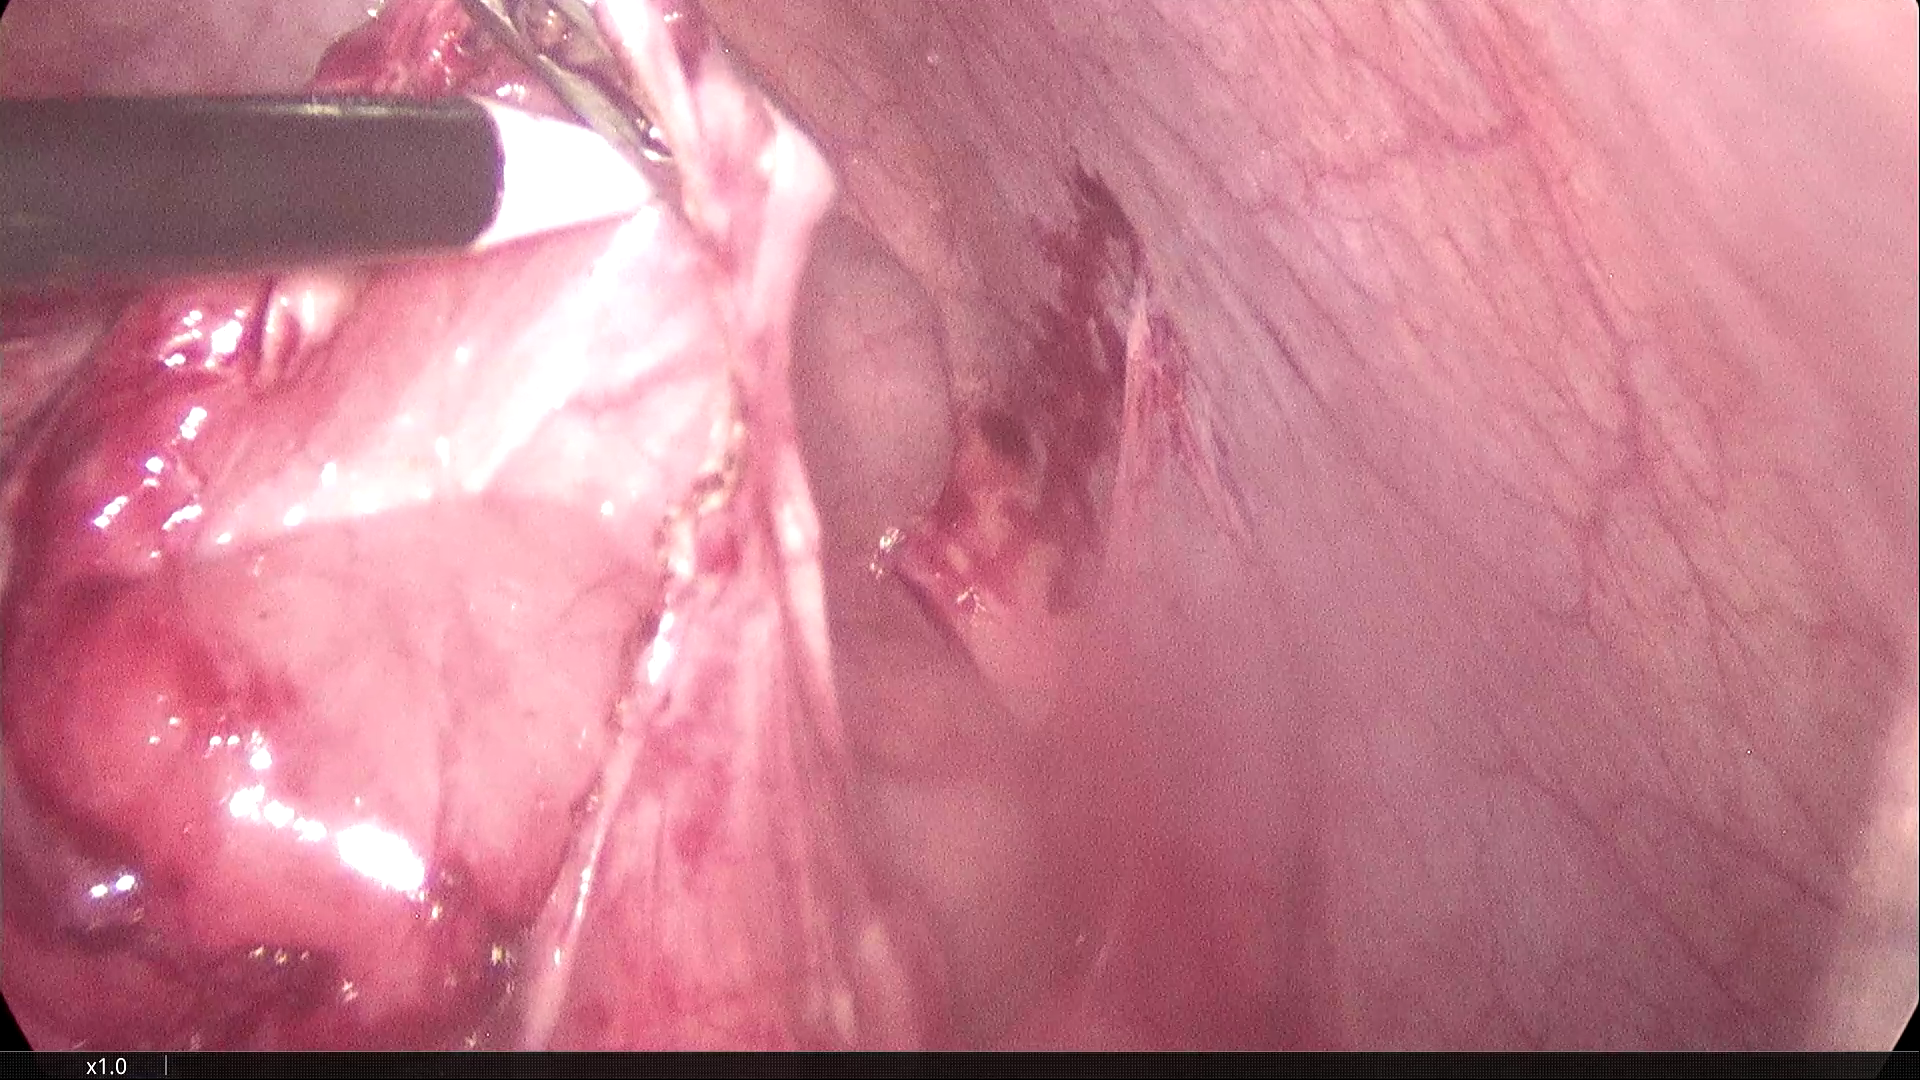

2021-3-31腹腔镜探查,脐部闭合穿刺置入腹腔镜,为观察孔。左下腹及下腹正中分别作操作孔,腹腔镜探查,腹膜光滑,腹腔无积液,胃肠道柔软,空回肠结肠无扩张。无游离大网膜,右下腹无游离肠襻,区域性的回肠肠襻为软膜样组织覆盖包裹,无明显炎症反应。包裹团块张力不高,内侧与乙状结肠系膜呈纤维组织粘连。锐性分离,无明显渗出。自后腹壁锐性切开包膜,显露其内迂曲回肠襻,形态大致正常,与包膜呈一般纤维组织性间隙,易于分离。包膜内肠管间有数条致密粘连纤维索带,予以切除。切除大部包膜组织,完全解放其中的回肠及阑尾远端部分。局部创面少许渗出,自回盲部顺序近端探查检视所有系膜小肠,见肠管及系膜自然正常形态,肠道畅通,未见憩室、肿物及外压扭转等病变。包膜包裹段回肠120cm,肠壁、系膜柔顺无损伤。直肠及盆腔未见明显异常,置腹腔引流管一根。

剥离包裹纤维膜,松解受困的回肠襻。